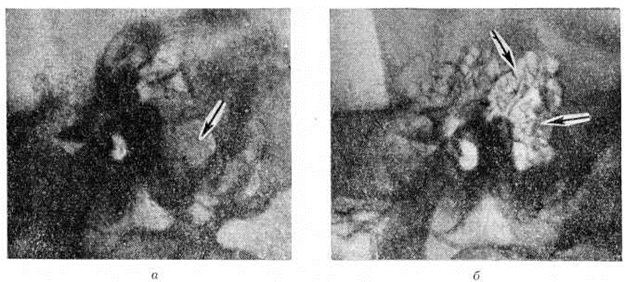

Классическим методом рентгенологическое исследования сосцевидного отростка является предложенная Шюллером (A. Schuller, 1905) рентгенография височной кости в боковой проекции (рисунок 1), а также предложенная Стенверсом (Н. W. Stenvers, 1928) рентгенография сосцевидного отростка в косой проекции (рисунок 2). Рентгенологические картина начальной экссудативной стадии острого Мастоидит характеризуется только затемнением сосцевидных ячеек; симптомы нарушения костной структуры отсутствуют. Резкое понижение воздушности ячеек приводит к снижению естественной контрастности снимка и затрудняет выявление тончайших костных перекладин между ячейками височной кости. В пролиферативно-альтеративной стадии Мастоидит с выраженным разрушением перекладин сосцевидных ячеек на рентгенограмме обнаруживается значительная потеря интенсивности линейных теней перекладин, а местами почти полное их отсутствие. При гнойном расплавлении перекладин и образовании абсцесса в сосцевидном отростке определяется очаг разрежения костной ткани. Очаг костной деструкции некоторое время может сохранять на рентгенограмме трабекулярную структуру, что объясняется наличием сохранившихся ячеек, окружающих полость абсцесса. При образовании субпериостального абсцесса с полным разрушением костной ткани просветление от деструктивного очага становится интенсивным и бесструктурным (рисунок 3). В период сохранения трабекулярности в области абсцесса, особенно небольшого, рентгенологическое распознавание его может представлять значительные трудности. Полость такого абсцесса в хорошо развитом пневматическом сосцевидном отростке ясно видна на томограммах височной кости.

Крупная одиночная ячейка в сосцевидном отростке (относительно редкий анатомический вариант), дающая в норме на рентгенограмме интенсивное просветление, может быть принята за Мастоидит с субпериостальным абсцессом (рисунок 4). Отличить полость субпериостального абсцесса от полости, вызванной холестеатомой в сосцевидном отростке, можно по характеру их границ. Полость субпериостального абсцесса, как правило, не имеет чётких очертаний, свойственных холестеатоме (смотри полный свод знаний). В сомнительных случаях диагностика проводится только путём клинико-рентгенологическое сопоставлений. Верхушечный Мастоидит (абсцесс Бецольда) может быть легко пропущен, если сделать одну боковую рентгенограмму височной кости (рисунок 5, а). При толстой наружной пластинке коркового вещества сосцевидного отростка костный дефект внутренней пластинки на боковом снимке не обнаруживается. На снимке в косой проекции по Стенверсу дефект этой пластинки выявляется чётко (рисунок 5, б). Для распознавания верхушечного Мастоидит очень важен учёт клинические, симптомов, определяющих тактику рентгенолога. Симптом полости рентгенологически нередко обнаруживается и при замаскированных Мастоидит при лечении антибиотиками. Рентгенологические наблюдение показывает, что консервативное лечение Мастоидит при благоприятных исходах ведёт к полной костной регенерации полости абсцесса и восстановлению воздушности сохранившихся ячеек. Серийное послойное рентгенологическое исследование височной кости таких больных указывает на замещение дефекта нормальной костной тканью (рисунок 6, а, б) и перестройку сосцевидного отростка, тип строения которого из распространённого пневматического становится смешанным спонгиозно-пневматическим. Рентгенологические наблюдения указывают на длительность этого процесса (1 — 2 года).